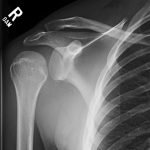

Radiographs demonstrated posterior displacement of the humeral head on the “Y” view (see white arrow) and widening of the glenohumeral joint space on anterior-posterior view (see red arrow). The findings were consistent with posterior dislocation and a Hill-Sachs type deformity.  Sedation was performed and reduction was attempted using external rotation, traction counter-traction. An immediate “pop” was felt during the procedure. Post-procedure radiographs revealed a persistent posterior subluxation with interlocking at posterior glenoid. CT revealed posterior dislocation with acute depressed impaction deformity medial to the biceps groove with the humeral head perched on the posterior glenoid, interlocked at reverse Hill-Sachs deformity (see blue arrow).